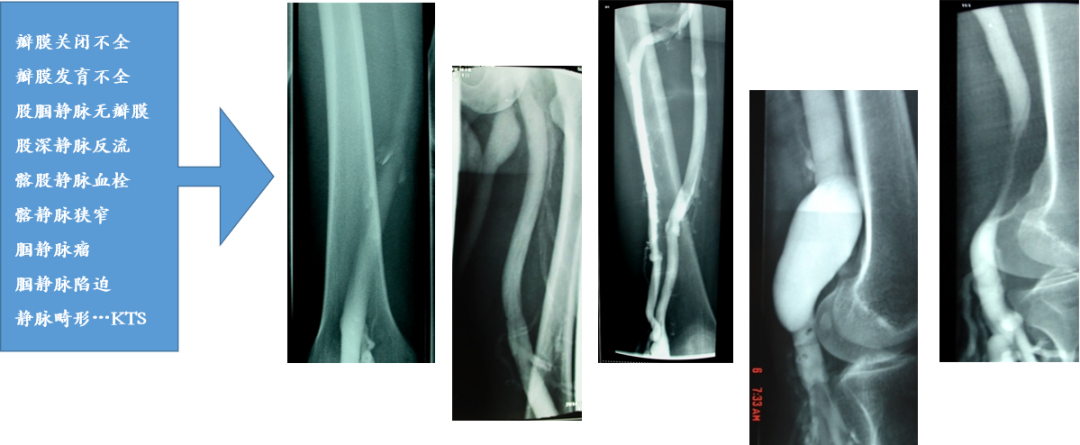

静脉造影检查结果

国外文献报道一组对16423条下肢静脉造影结果:深静脉功能不全 86.6%,单纯大隐静脉曲张13.4%

上海九院11073名浅静脉曲张病人行静脉造影证实:原发性深静脉功能不全 56%,继发性深静脉功能不全29%,单纯大隐静脉曲张12%

我们对 3146 例 C4~C6 病人行下肢深静脉造影检查发现: 89%病人深静脉重度反流 Kinstner Ⅲ~Ⅳ级Brake M. JVS 2013;860-868 张培华,临床血管外科学

9731例深静脉造影发现